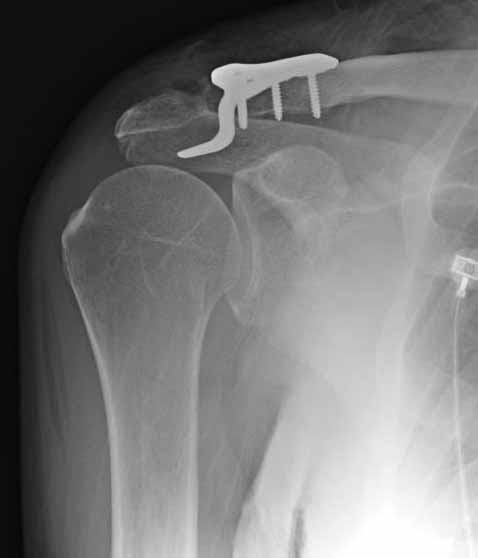

Из заданного вопроса в этом посте я понял, что разговор идет по поводу “методики применения ключичной пластины с крючком при акромиальных переломах”, т.е не ведется разговор “по поводу лечения косых переломов ключицы”.

Если так, тогда Юрий прав, методов лечения акромиона пластинами нельзя было найти. Обычно изобретали из реконструкционных пластин 2.7 или 2.4 мм толщиной. Такая фиксация адекватно удерживает перелом акромиона. Только недавно компания Acumed создала пластину для переломов акромиона, здесь линк: http://www.acumed.net/sites/default/files/literature/brochure-surgical-technique/CPS00-11-A.pdf.

По поводу пластины с крючком, Ваше заключение "не вижу препятствий для фиксации акромиального косого перелома ключицы для МОС использовать пластинку с крючком" вызывает сомнение.

Предназначенную для лечения повреждений связочного аппарата акромиально-ключичного сочленения пластину можно применить не при всех переломах акромиального конца ключицы. Потому что имплант рассчитан на интактную ключицу и не для переломов ключицы. Пластина короткая, не покрывает медиальный диафизарный фрагмент ключицы и за счет тракции стерноклеидомастоидеус такая фиксация прорвется через несколько дней.